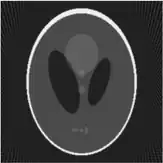

If a function represents an unknown density, then the Radon transform represents the projection data obtained as the output of a tomographic scan. Hence the inverse of the Radon transform can be used to reconstruct the original density from the projection data, and thus it forms the mathematical underpinning for tomographic reconstruction, also known as iterative reconstruction.

The process of reconstruction produces the image (or function in the previous section) from its projection data. Reconstruction is an inverse problem.

Iterative reconstruction methods

Compared with the Filtered Back-projection method, iterative reconstruction costs large computation time, limiting its practical use. However, due to the ill-posedness of Radon Inversion, the Filtered Back-projection method may be infeasible in the presence of discontinuity or noise. Iterative reconstruction methods (e.g. iterative Sparse Asymptotic Minimum Variance[10]) could provide metal artefact reduction, noise and dose reduction for the reconstructed result that attract much research interest around the world.